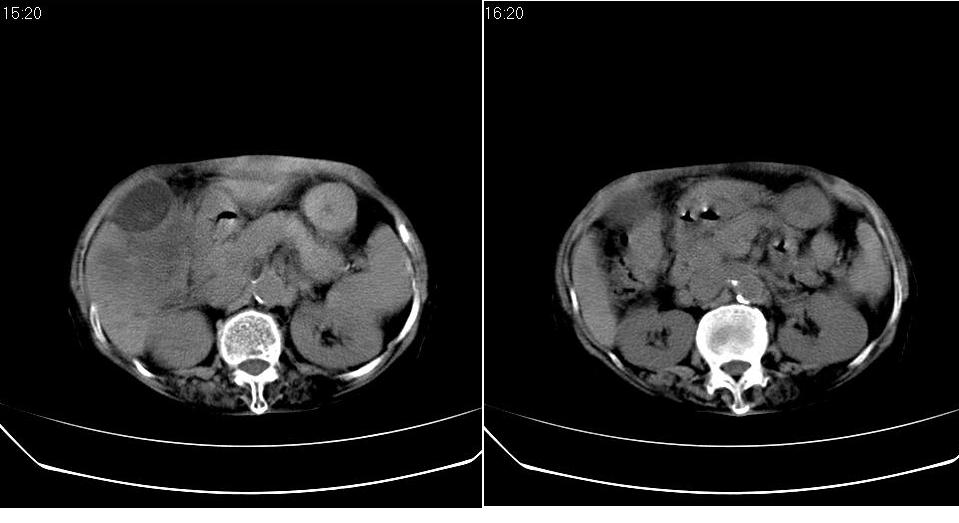

标题: CT23701:上腹部CT平扫

女 76岁,腹痛十余天。

肝癌伴肝内胆管扩张,建议增强.

肝内胆管扩张,综合考虑胆管细胞肝ca!

考虑肝癌(胆管细胞型?)并肝内胆管扩张。